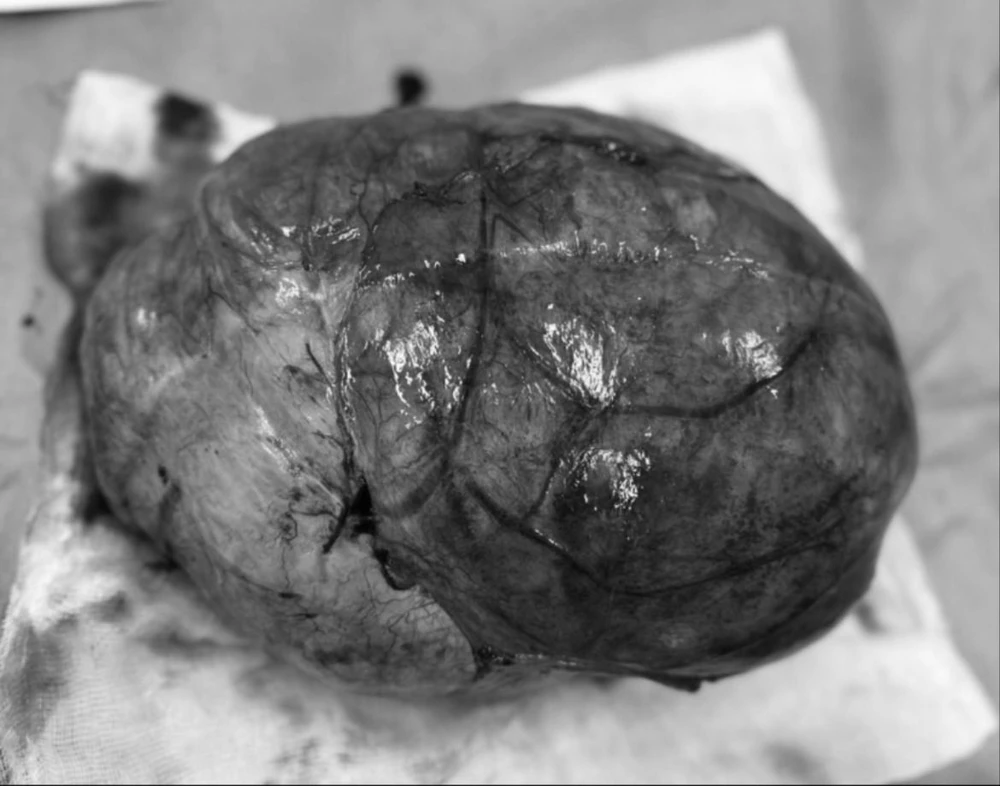

Sau 2 giờ phẫu thuật căng thẳng, các bác sĩ đã bóc tách hoàn toàn khối u xơ có kích thước lớn 30 x 25 cm, bảo tồn được tử cung cho bệnh nhân.

Khối u xơ tử cung lớn khiến bệnh nhân như mang bầu 40 tuần. Ảnh: BVCC